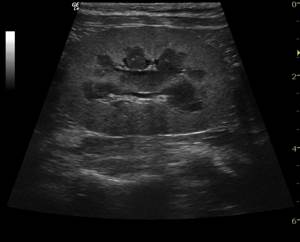

При диагностике собак с подозрением на заболевания почек проводится тщательный сбор анамнеза, общий осмотр, клинический и биохимический анализ крови, анализ мочи, ультразвуковое и рентгенографическое исследование органов брюшной полости. Дополнительную информацию о почечной функции может дать рентген с внутривенным контрастированием (выделительная урография).